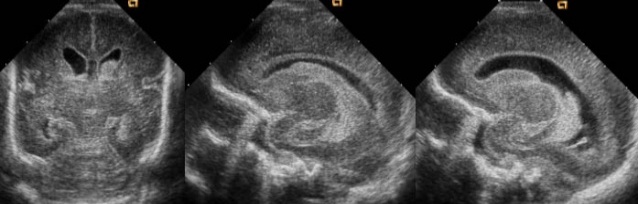

Transcranial and transfontanel ultrasound, also known as cranial ultrasound, uses sound waves to obtain images of the brain and the ventricles filled with cerebrospinal fluid located in the deeper parts of the brain.

This imaging test is mostly done in infants. It can be used to check the ventricles in babies up to 18 months old and to address issues related to premature birth.

For routine screening, the anterior fontanel serves as an acoustic window. Additional acoustic windows used to image specific intracranial structures include: the posterior fontanel, mastoid fontanel, squamous portion of the temporal bone (i.e., temporal window), foramen magnum, coronal suture, and squamous sutures.

A basic routine screening is performed through the anterior fontanel. To be clear, the brain of a premature newborn (i.e., 28 weeks or less) will appear less developed than that of a term newborn, including less convoluted gyri and shallower sulci; the following should only serve as a rough guide.

In a coronal (transverse) scan, the transducer is first tilted forward, then gradually tilted backward.